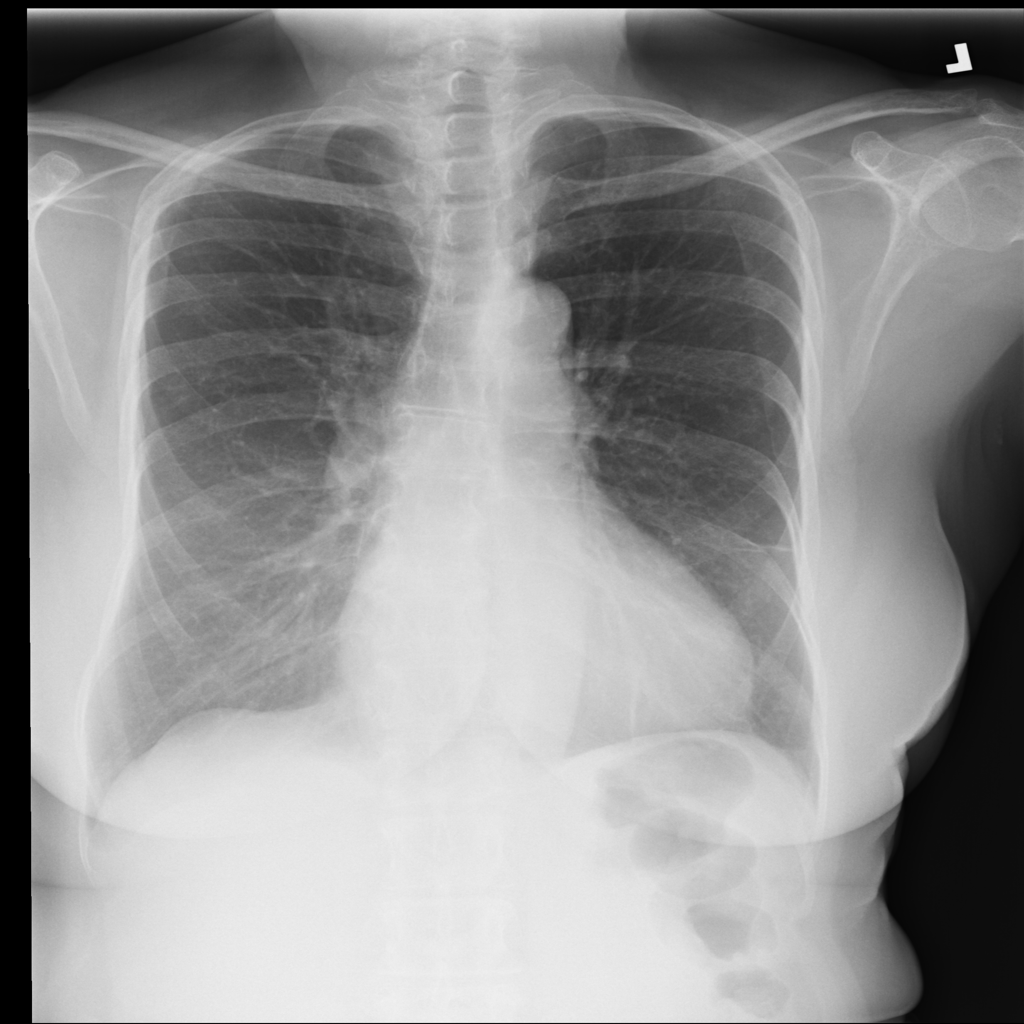

PAT-B0DB · IMG-003Emphysema

PAT-B0DB · IMG-003

PA